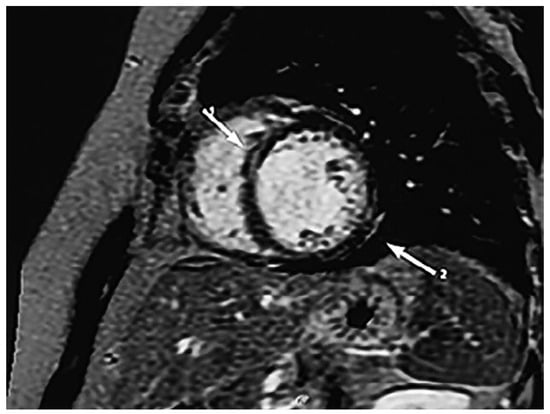

Diagnostic assessment